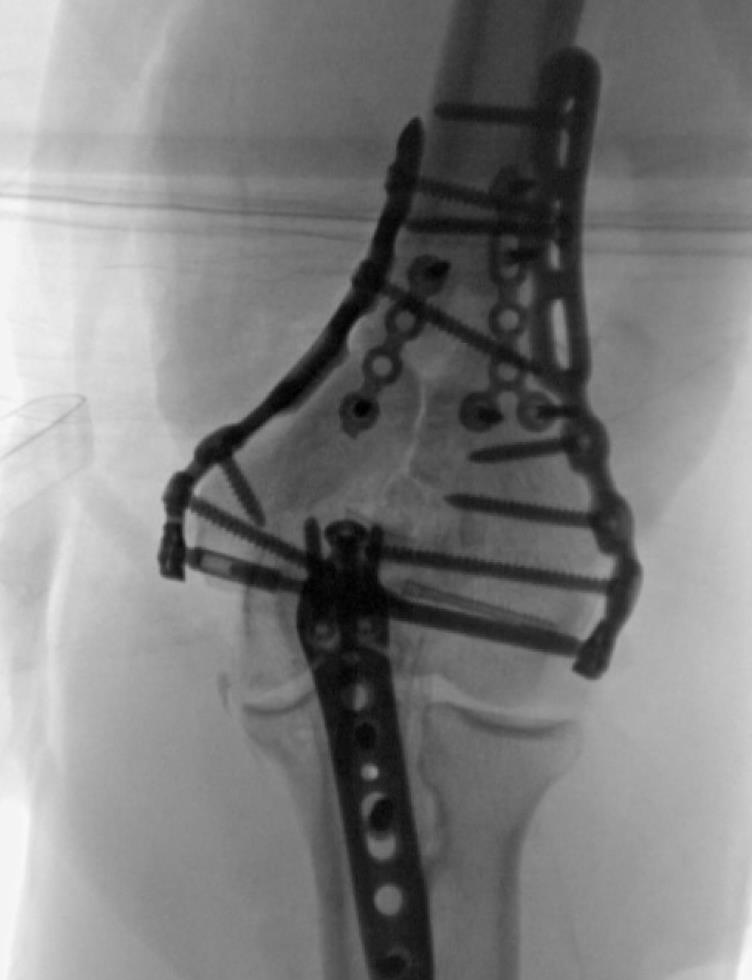

• TiBeam® Assembly

• Use Trochlea Compression Screw Insertion Tool to push out the trochlea K-Wire.

• Place Female Trochlea Compression Screw on the tool tip to protect internal threads.

• With T-10 Driver, insert the female TiBeam® component while pulling the Insertion Tool until fully seated.

• Remove the Insertion Tool and insert the male TiBeam®.

• TiBeam® Compression

• With both drivers in place, engage the male and female components and compress the trochlea fragments.

• Confirm TiBeam® engagement and compression with fluoroscopy.

• Trochlea support screws - medial plate

• Remove the provisional fixation from the Epicondylar Holes and perform final fixation with the chosen Screws.

• Starting with the third hole of the medial plate, work proximally to finish inserting all Metaphyseal Screws

• Repeat for lateral side.

• Diaphyseal function

• Fill the remaining holes in the humeral shaft FreeFix® slots with 3.5mm locking or compression screws using the HPS or 3.5mm Thread-In Drill Guide, and 2.7mm x 50mm Drill Bit.

• When reduction is complete, insert a Locking Cap into each distal node to create a fixed TiBeam® construct.